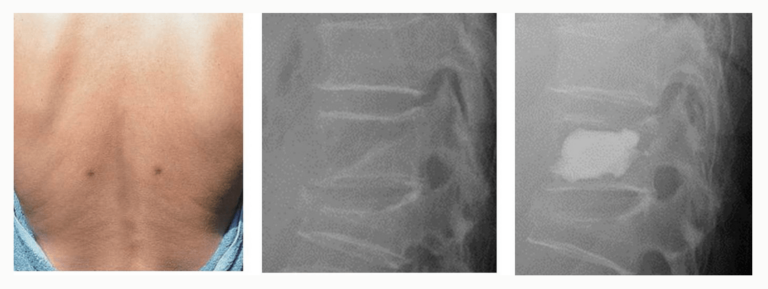

経皮的椎体形成術(BKP)

- 骨粗鬆症による椎体圧迫骨折が対象

- 5mm程度の小切開を2か所 創部痛は最小限です。

- バルーンで椎体を整復し、骨セメントで安定化

- 保険適用・低侵襲手術